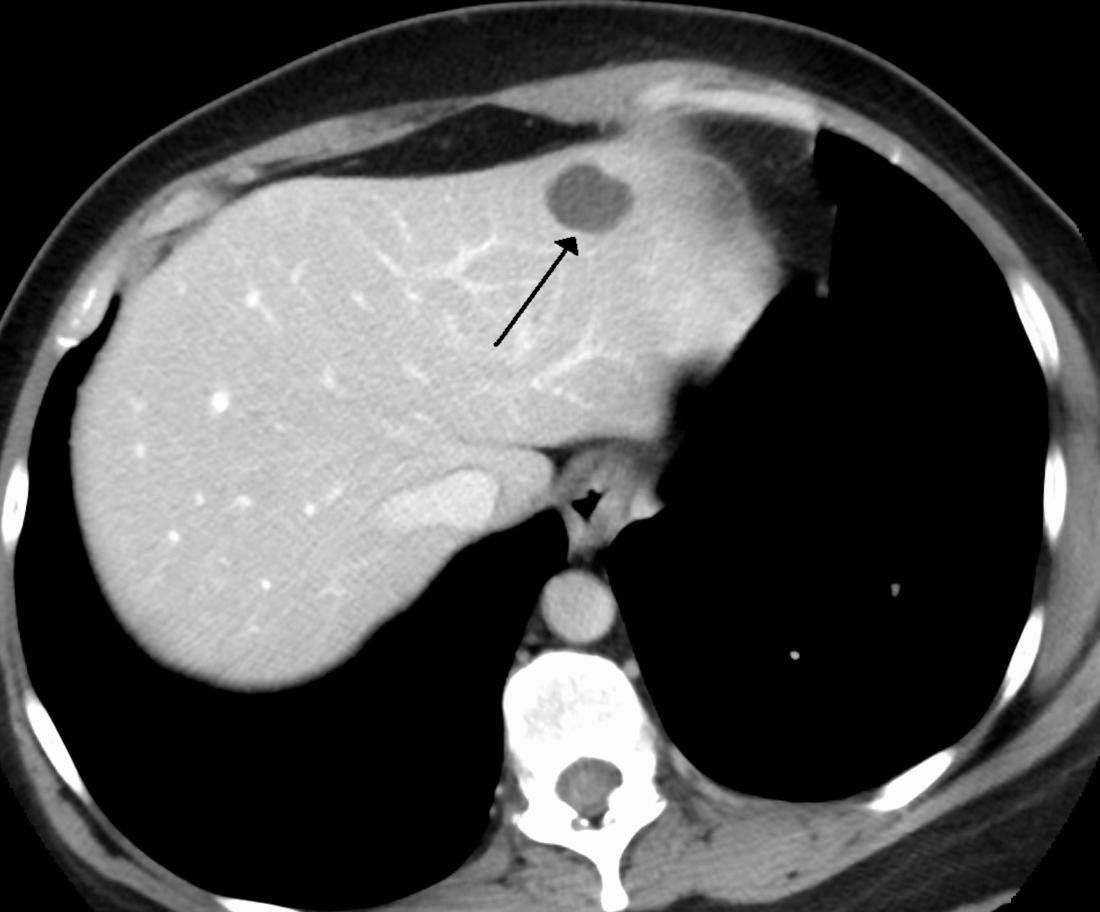

CT

要看清楚我们,CT检查是更清楚的。在CT下的我们,也是边界清楚的,呈低密度的肿块。大约10%的我们,可以同时发现里面有一些钙化灶。

磁共振

磁共振是更准确的无创性检查,检查的敏感性和特异性都是很高的,表现为呈边界清楚的、光滑的、均匀性质的肿块。但也有一些会跟血液供应丰富的癌症转移灶类似,要引起注意。